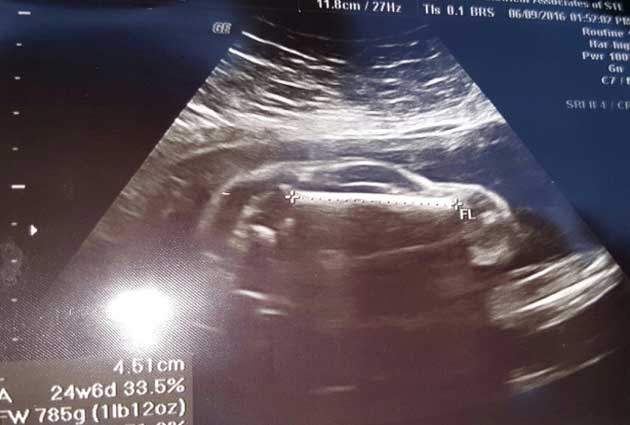

प्रेग्नेंट बीवी का अल्ट्रासाउंड कराने गए शख्स के उड़े होश, बच्चे की जगह दिखी स्पोर्ट्स कार

आमतौर पर जब भी कोई दम्पति डॉक्टर के पास क्लीनिक में अल्ट्रासाउंड करवाने जाता है, तो उनके मन में कुछ सवाल होते हैं। उनका होने वाला बच्चा पेट में क्या कर रहा होगा, कैसा दिखता होगा? मगर आप सोचिए कि आप अपनी बीवी को लेकर डॉक्टर के पास जाएं और वो कहे कि मुबारक हो, आप एक स्पोर्ट्स कार के बाप बनने वाले हैं।

वह जब अपनी प्रेग्नेंट बीवी का चेकअप करवाने डॉक्टर के पास गया, तो अल्ट्रासाउंड में पेट के अन्दर एक स्पोर्ट्स कार जैसी आकृति दिखाई दी। यह देखकर पति-पत्नी दोनों चौंक गये। आपकी और मेरी तरह वो भी उस समय यही सोचने लगे, 'ऐसा कैसे हो सकता है।'

जब पता चला कि पेट में कार नहीं, उनका बेबी ही है। बस उसकी आकृति इस समय कार जैसी दिख रही है, तब उनकी जान में जान आई। उनका कहना था, 'एक तो वो पहले से ही आश्चर्य में है कि उनकी बीवी दोबारा इतनी जल्दी प्रेग्नेंट कैसे ही गई, जबकि उनके पहले बच्चे को पैदा हुए अभी 6 महीने ही हुए हैं और अब पेट में स्पोर्ट्स कार दिख रही है।'

उन्होंने तुरन्त ही अल्ट्रासाउंड की फोटोज सोशल मीडिया पर शेयर कर डालीं, जिस पर लोगों के मजेदार कमेन्ट भी आए।